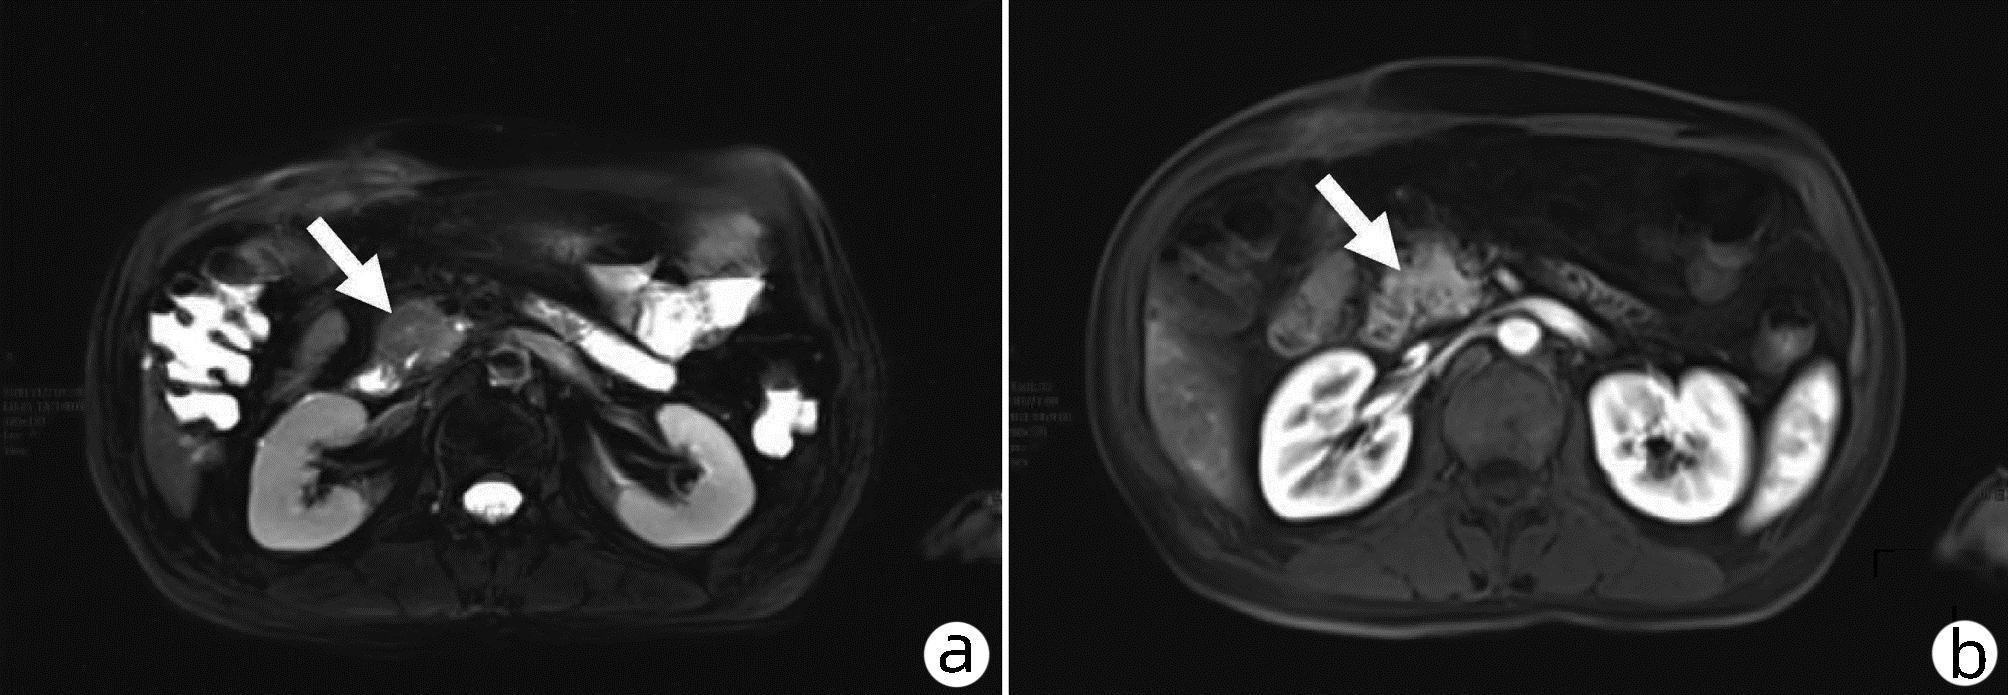

肝窦阻塞综合征合并胰周积液误诊为急性胰腺炎1例报告

陈佼舜, 张浩翔, 殷涛

2022, 38(10): 2341-2343. DOI: 10.3969/j.issn.1001-5256.2022.10.026

摘要(874) HTML (241) PDF (2266KB)(78)

摘要: